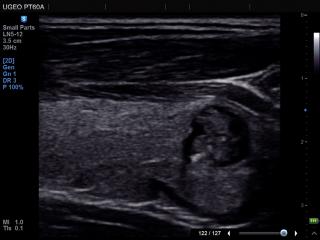

УЗИ аппарат Samsung PT60 (снят с производства)

PT60A - портативный ультразвуковой аппарат с цветным допплером и современными технологиями, разработанный инженерами компании Samsung для работы в операционной, неотложной помощи, интенсивной терапии и спортивной медицины, может использоваться и в других областях.

Линейный датчик 5-12 МГц

Поверхностные структуры (щитовидная железа, молочная железа, лимфоузлы), мускулоскелетные исследования (суставы, мышцы, подкожные структуры), периферические сосуды.